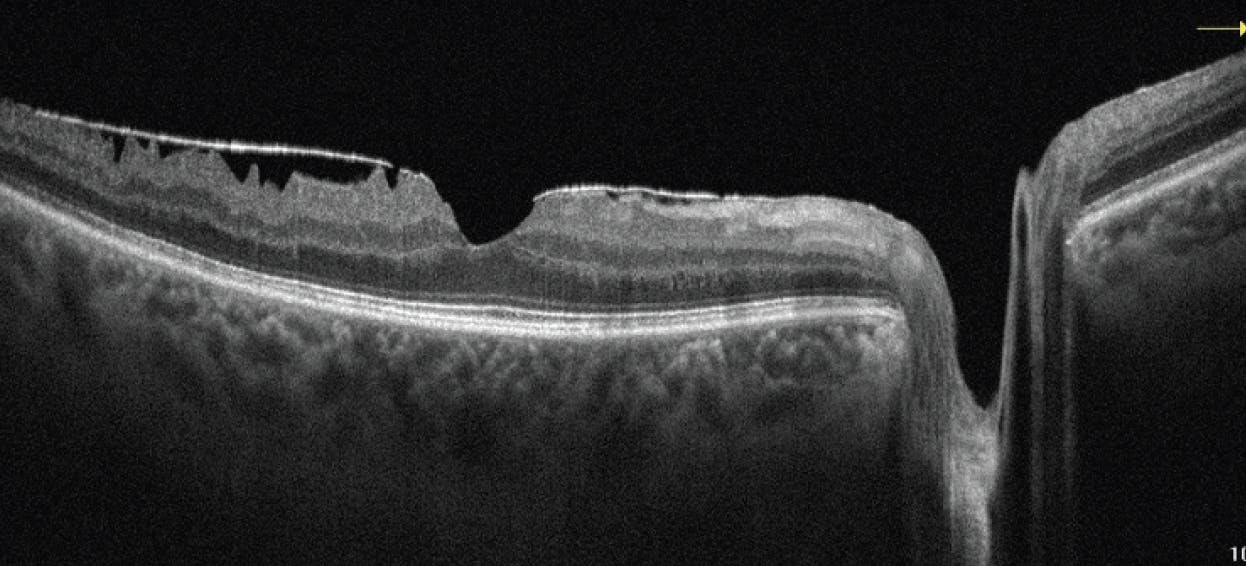

ERM and anomalous PVD may result in extended periods of vitreous contraction leading to VMT. VMT occurs when the posterior cortical vitreous partially separates from the retina and causes anteroposterior traction at the fovea.11 The tractional forces result in anatomic obscuration of the retina and may cause intraretinal pseudocyst formation and other complications, including retinal thickening, distortion, or neurosensory detachments (Figure 4).6 VMT is most common in the elderly population and in women, due to age-related vitreous changes and vitreous liquefaction associated with declining post-menopausal estrogen levels.12

VMT can be classified by the width of the vitreous attachment; focal VMT is defined as < 1,500 µm, and broad VMT is defined as > 1,500 µm. It is important to comment on the size of the VMT, as broad VMT is more likely to result in overall retinal thickening and intraretinal schisis, whereby focal VMT is associated with pseudocyst formation, foveal elevation, and FTMH formation.6

VMT is also categorized by the presence or absence of other comorbidities. An OCT with only VMT and no other pathology is termed isolated VMT, whereby an eye with VMT and other abnormalities is termed concurrent VMT. Treatment for VMT includes observation, pars plana vitrectomy, ocriplasmin (Jetrea, Inceptua), and/or pneumatic vitreolysis.